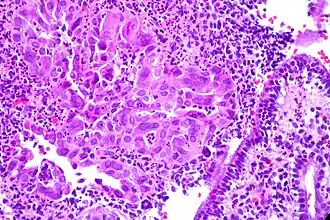

Цервицит — воспалительное заболевание шейки матки[3]. Выделяют несколько разновидностей в зависимости от места локализации и вызвавшего процесс микроорганизма. О наличии или отсутствии заболевания судят по результатам анализов и количеству выявленных патогенных агентов, занесенных, обычно, извне, например, при половом контакте. Хроническое течение заболевания может способствовать развитию утолщения или же истончению слизистого и других слоев шейки матки и стать пусковым механизмом для распространения инфекционных заболеваний.

Часто заболевание протекает бессимптомно, но некоторые женщины жалуются на патологические боли и межменструальные вагинальные кровотечения. Цервицит может сопровождаться эндометритом, поэтому у женщин с новым эпизодом цервицита следует оценивать признаки ВЗОМТ (воспалительные заболевания органов малого таза), а также проводить тестирование на хламидию и гонорею методом ПЦР, на наличие бактериального вагиноза и трихомониаз. Поскольку чувствительность микроскопии для обнаружения трихомонады является относительно низкой (примерно 50 %), симптомные женщины с цервицитом при отрицательной микроскопии для обнаружения трихомонад должны проходить дальнейшее тестирование (культуральный метод или ПЦР). Наличие > 10 лейкоцитов в поле зрения в вагинальном содержимом в отсутствие трихомониаза может указывать на цервицит хламидийной этиологии[4].